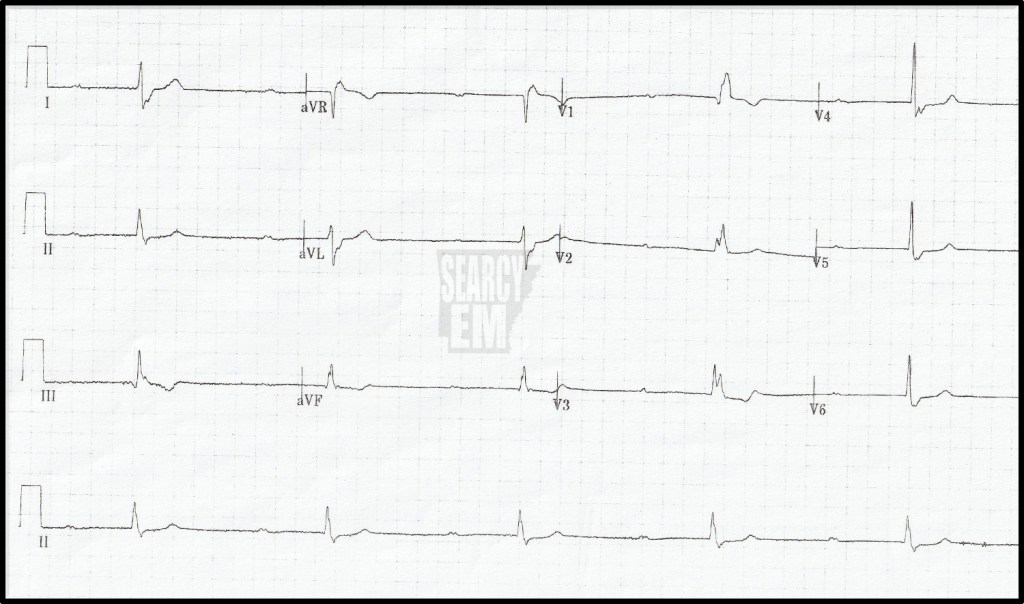

57 Interpretation

Sinus with ST depression in the anterior leads. Concerning for anterior ischemia vs posterior infarction.

The same patient as EKG 57. In this tracing, leads V4, V5, and V6 have been moved to positions V7, V8, and V9. The depression remains in the anterior leads (V2, V3), but now we see ST elevation in leads V7-V9). This is a posterior STEMI. You can see that the leads 7, 8, and 9 were hand written in on the tracing as the machine does not know that the leads were moved.